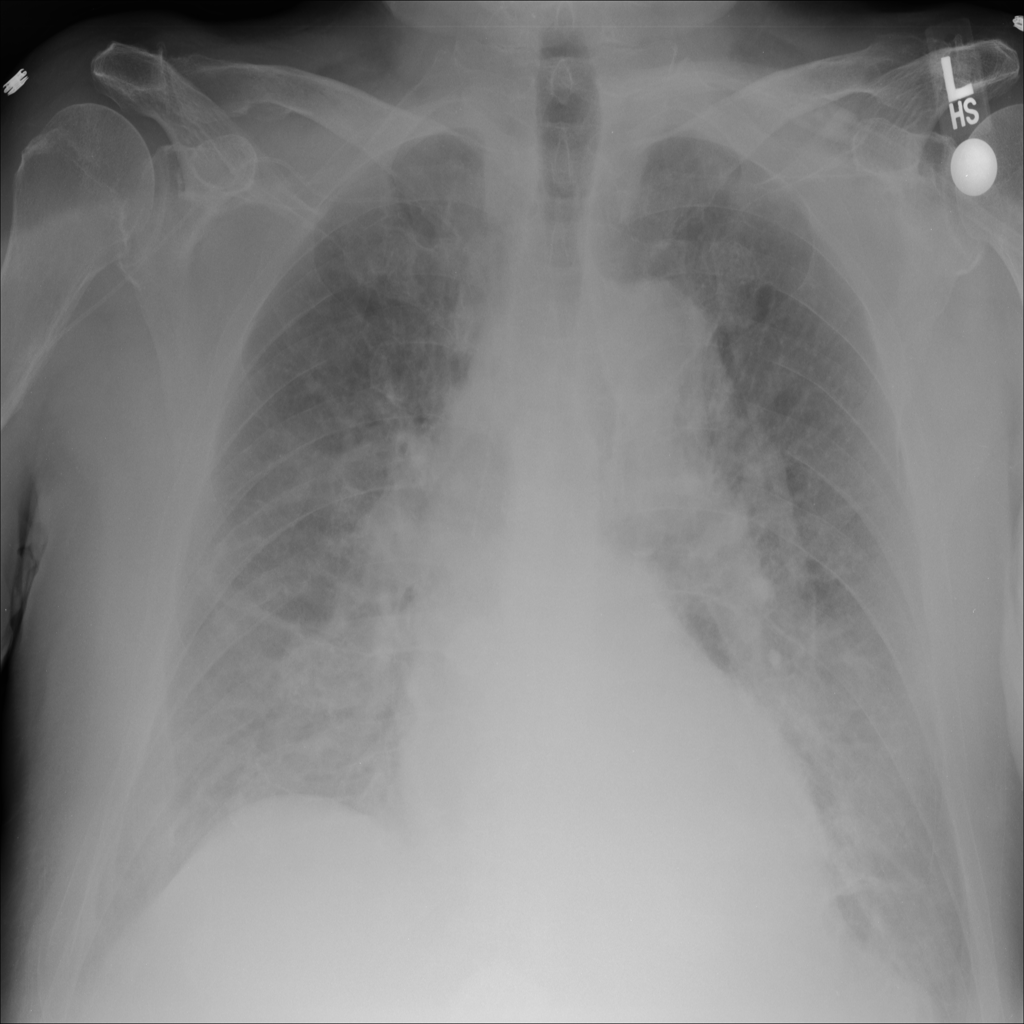

PAT-5B86 · IMG-009Edema

PAT-5B86 · IMG-009

PA